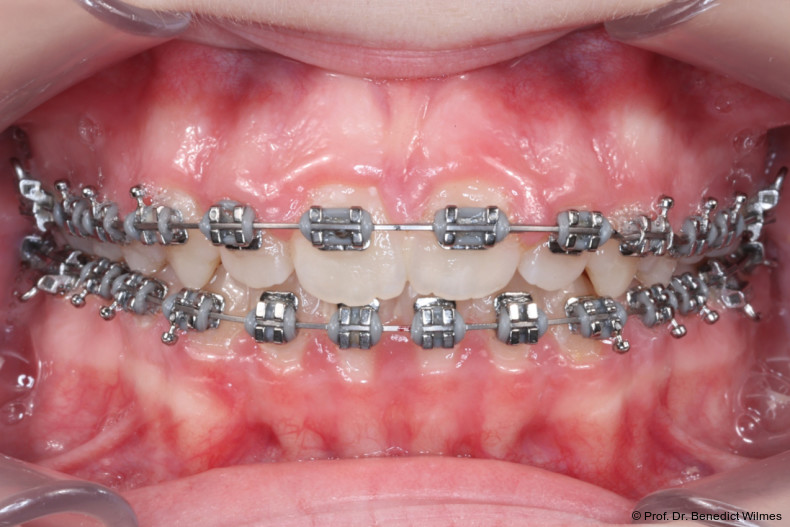

Nach erfolgreicher Expansion und Molaren­intrusion wurde eine Multibracket-Therapie zur Ausformung und Koordination der Zahnbögen durchgeführt (Abb. 8a–f). Nach Abschluss der aktiven Behandlungsphase wurden die Apparaturen entfernt und festsitzende Retainer im Ober- und Unterkiefer eingesetzt (Abb. 9a–k).